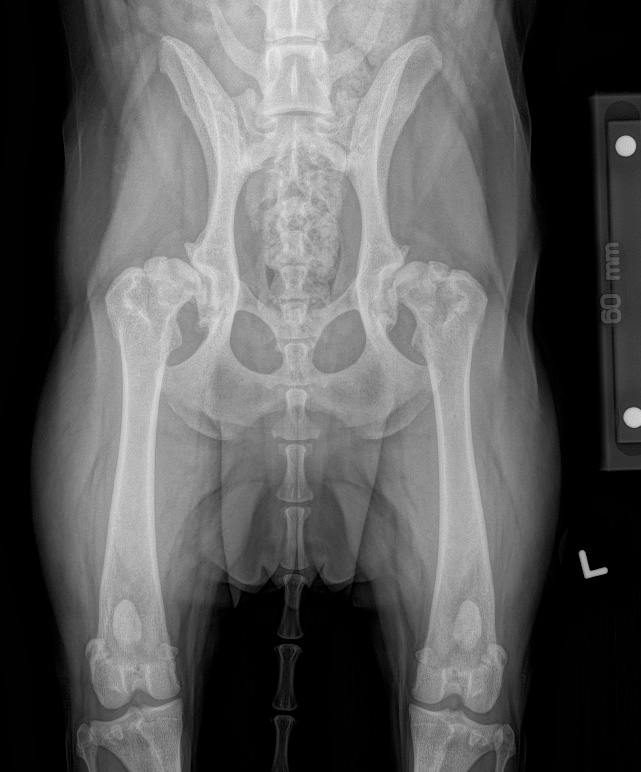

Anatomy of canine hip dysplasia. Notes ( A C ) Canine hipextended Hip Dysplasia Dogs Vca Hip dysplasia is a multifactorial abnormal development of the coxofemoral joint in dogs that is characterized by joint laxity and subsequent. View information on hip dysplasia in dogs, as well as screening and treatment options. The hip joint laxity is responsible for. Small dogs and lean, slender breeds such as sighthounds rarely. Learn what all owners should know about hip. Hip Dysplasia Dogs Vca.